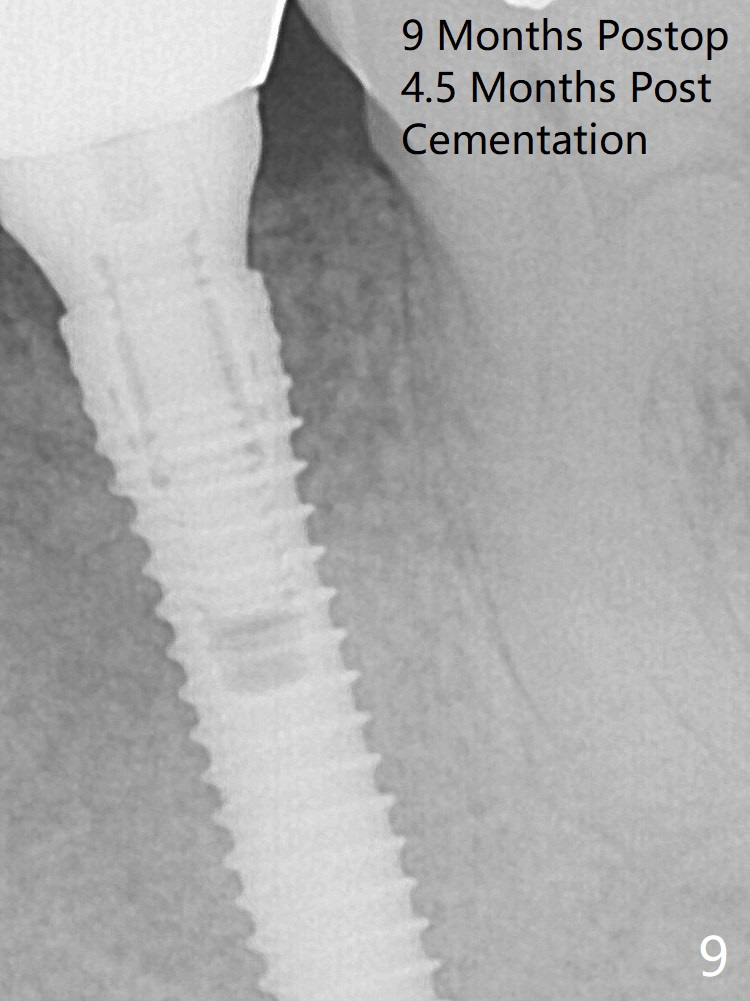

It appears that a 3.8x18 mm implant is not placed deep enough. Following 3-4 more turns of the implant and placement of a 5.5x4(3) mm abutment (Fig.5 A), allograft is placed (*). The bone around the implant appears to have regenerated 4 months postop (Fig.7). Bone density appears to continue increasing 9 months postop (i.e., 4.5 months post cementation, Fig.9).